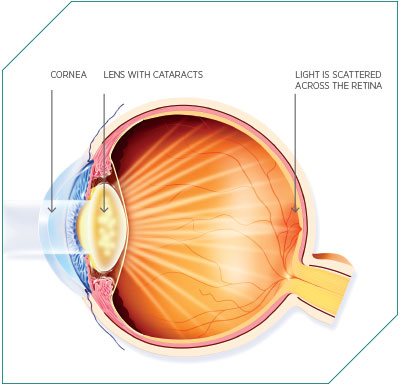

Type 1 diabetes occurs when the pancreas, a small gland located behind the stomach, fails to produce the correct level of insulin a person needs. Insulin is a hormone that maintains blood-glucose levels in the body, and subsequently energy levels. If the body is failing to manage its energy levels correctly, it leads to a range of short-term problems, such as tiredness and weight loss. Long term, the effects are far more damaging, with potential issues ranging from kidney disease, heart disease, blindness and possible limb amputation. Apart from injections of insulin to keep levels correct, alternative treatments are often underdeveloped: an insulin pump via which the hormone can be administered, for example, is only practical for a relatively small number of patients. Another therapy alternative has been the transplantation of pancreatic islets. This solution might seem like an obvious one, but logistically it has always been impractical; as with any transplant therapy, there is a constant shortage of donors. Public awareness and education programmes can only go so far. However, a new source of cells is being investigated.